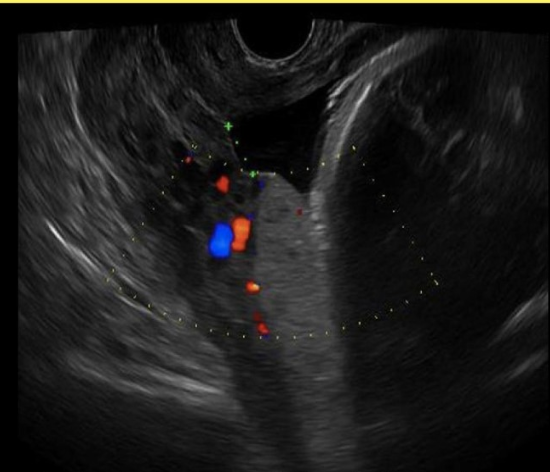

chorioangioma is supected. which image shows it

a) A